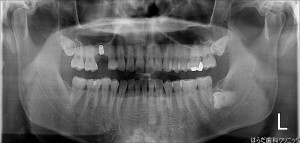

本日は杉村先生による右上5番のインプラントオペが行われました。

オペを行う前と後にはレントゲン写真を撮り状態のチェック、確認を致しますので何か心配な事、気になる事にも迅速に対応致します。